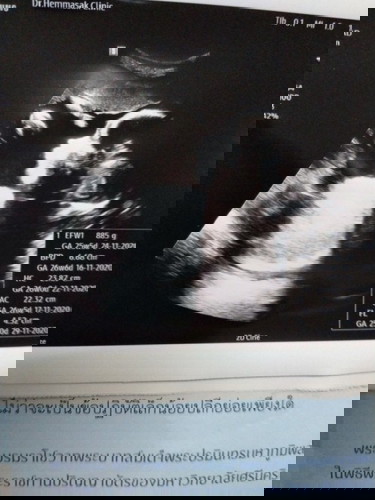

29 สัปดาห์ ลูกดิ้นน้อยลงค่ะ

คุณแม่ท่านไหนเป็นไหมค่ะ ดิ้นน้อยลง แต่ดิ้นแรงตอนได้ยินเสียงดังๆๆๆ